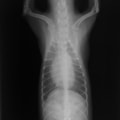

症例1:【マルチーズ 12歳齢 去勢オス】

A:胸部レントゲン写真 正面像

胸部レントゲン検査において重度の心拡大と肺水腫が認められた。超音波検査では、重度の僧帽弁閉鎖不全症、三尖弁閉鎖不全症、中程度の大動脈弁閉鎖不全症を合併していることが判明した。三尖弁逆流速度から肺高血圧症が示唆された。